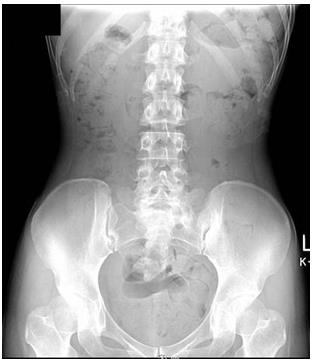

腹部X线检查(俯卧)

体型偏瘦。大便中有空气,可推断粪便停滞。从盲肠到横结肠,降结肠,乙状结肠,直肠,以及直肠到结肠部分都有粪便停滞。诊断宿便过多。